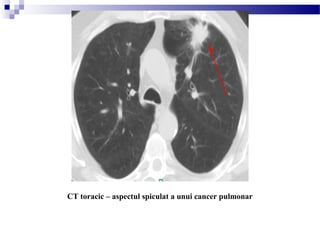

CT toracic – aspectul spiculat a unui cancer pulmonar

Cele ase tipuri principale de carcinoame pulmonare cu aspectș

tipic sunt:

o adenocarcinomul – (35-50%) periferic, cu inciden a mare deț

metastazare timpurie

o cu celule scuamoase – (30%) central, cu implicare hilară, cavitația

este obi nuită,ș cre tere lentăș

o cu celule mici - (15-20%) central, cavitația este rară, adesea trăsătura

dominantă este prezen a maselor mediastinale i hilare, cre tere rapidăț ș ș

i metastazare precoce.ș

ocu celule mari – (10-15%) periferic, dimensiuni

mari, cavitația este prezentă

obronhoveolar – (3%) periferic, aspect rotunjit,

infiltrat asemănător celui din pneumonie (bronhograme

aerice), ocazional multifocal

ocarcinoid – (mai pu in deț 1%) tipic se prezintă sub

forma unei leziuni endobron ice bine definită;ș

metastazele ganglionare ale ficatului si creierului se pot

intensifica dens.